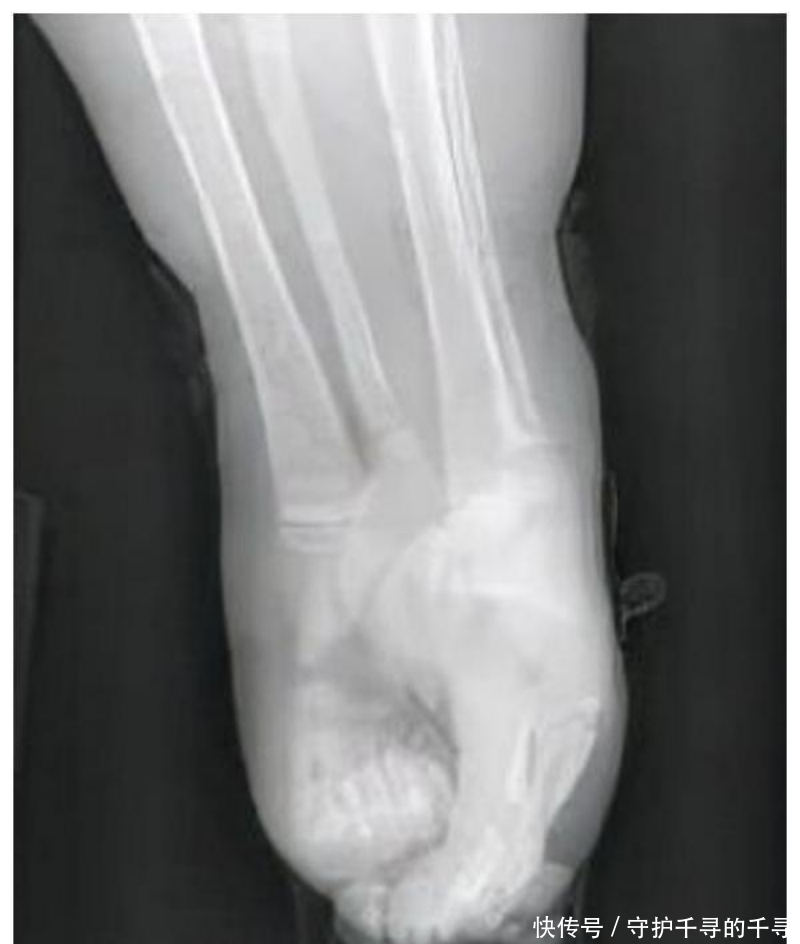

“美人鱼”女孩:8年做150次手术,被断言活不过1岁,却活了